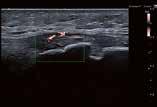

Hochauflösender Ultraschall in der Sportpraxis

Wie kamen Sie zur Sonographie?